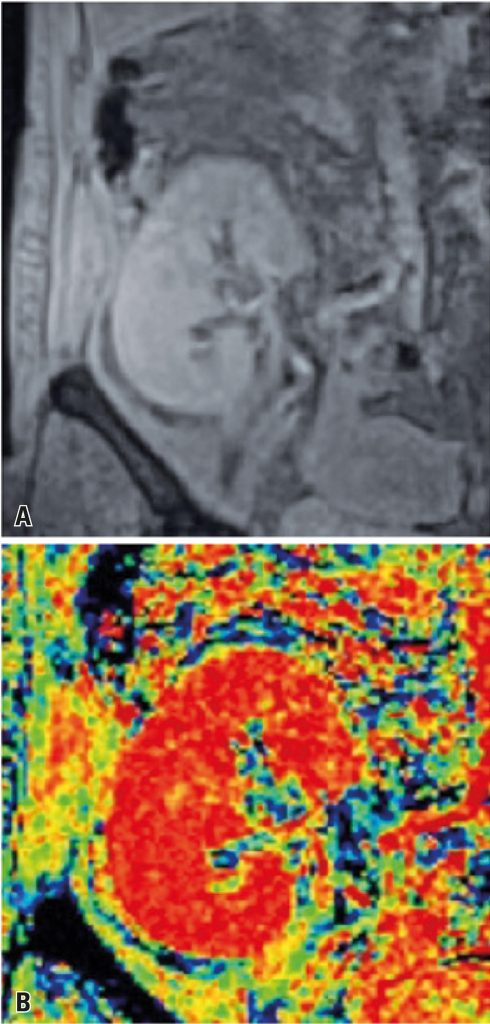

Avaliação da sequência dependente do nível de oxigênio no sangue (BOLD) com dispositivo 3 Tesla em pacientes transplantados renais na avaliação da disfunção de enxerto precoce, correlacionada com biópsia

Avaliar a sequência de ressonância magnética blood-oxygen-level-dependent (BOLD) realizada em um equipamento 3 Tesla para medir a biodisponibilidade do oxigênio do tecido pelo valor de R2* na diferenciação de necrose tubular aguda e rejeição aguda, comparando à biópsia renal (padrão-ouro).

Estudo unicêntrico, prospectivo, com pacientes submetidos a transplante renal de 2013 a 2014, que desenvolveram disfunção do enxerto menos de 4 semanas após o transplante. Todos os pacientes foram submetidos à ressonância magnética abdominal 3 Tesla com o mesmo protocolo, seguida de duas sequências BOLD e biópsia renal.

Foram incluídos 12 homens (68,75%) e três mulheres (31,25%). Foram realizadas 19 biópsias renais percutâneas (quatro pacientes necessitaram de segunda biópsia devido à alteração nos achados clínicos). Os resultados histopatológicos incluíram dez casos de necrose tubular aguda, quatro de rejeição aguda e cinco casos de outros diagnósticos (miscelânea). A comparação entre os quatro grupos de interesse não mostrou diferenças significativas em relação ao R2* no córtex (p=0,177). Quanto ao R2* da medula, observaram-se diferenças significativas (p=0,033), com miscelânea e necrose tubular aguda apresentando valores mais baixos quando comparados aos demais.

A ressonância magnética BOLD 3 Tesla é uma técnica viável que indiretamente utiliza a concentração de oxigênio no tecido em enxertos renais e pode ser usada para a diferenciação entre rejeição aguda e necrose tubular aguda.